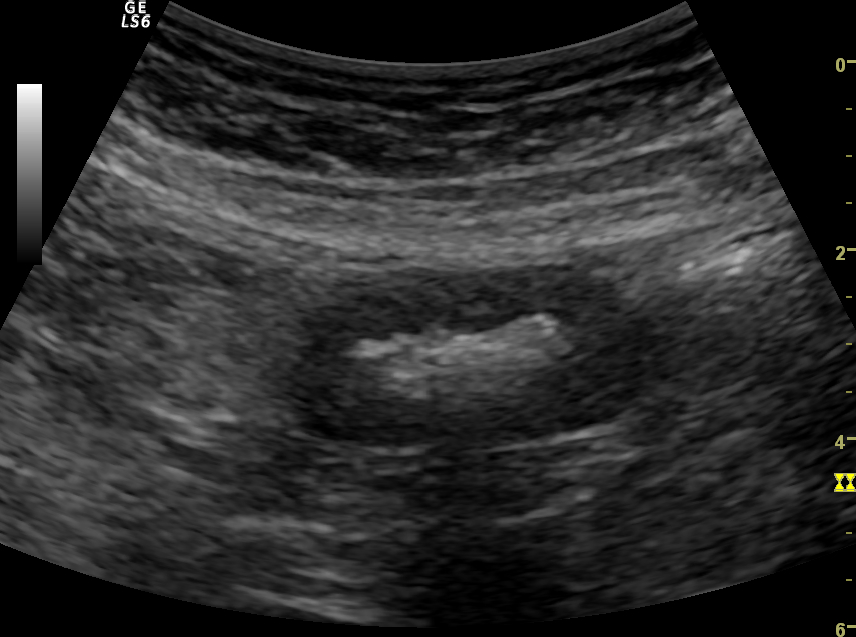

Acute abdominal pain is one of the most common conditions encountered in the emergency department. The differential diagnosis of acute abdominal pain is extensive and identifying the underlying etiology can be challenging. We report a case of acute transient ischemic jejunitis due to symptomatic isolated superior mesenteric artery dissection in a patient with no cardiovascular risk factors or autoimmune diseases. Symptomatic isolated superior mesenteric artery dissection is a rare cause of acute abdominal pain usually treated in the surgical department. The patient had criteria for conservative treatment and rapidly recovered. We highlight a rare condition which should be taken into account for the differential diagnosis of acute abdominal pain.